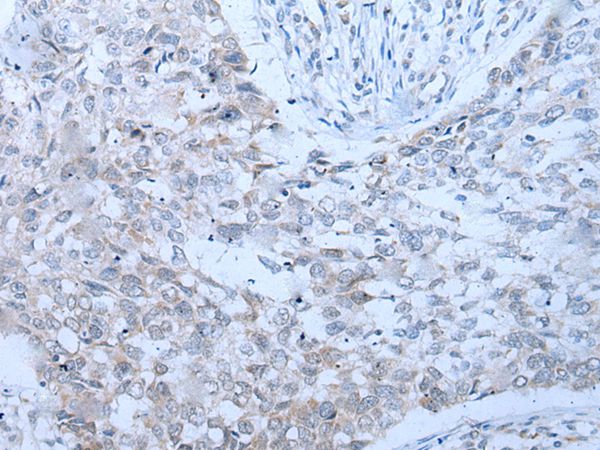

分类: 科研抗体货号: P43448别名: D52; N8L; PC-1; PrLZ; hD52应用: WB,IHC反应种属: Human